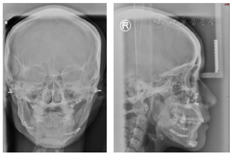

口外检查(图1):

正面观:下颌不对称,颏部右偏6 mm,微笑时露齿不足,咬合平面左低右高。

侧面观:直面型,双侧下颌升支形态不一致。

开口型左偏,开口度正常。

头颅正、侧位片检查(图4):治疗前头正片显示下颌右偏,治疗前头侧片显示骨性Ⅰ类均角。